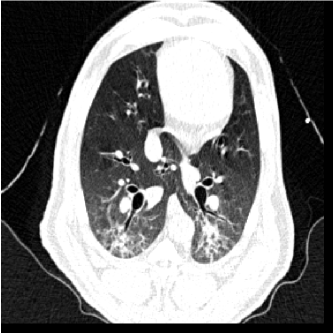

For each animal, approximately 200 automatically identified landmarks within the lungs are used to compute registration accuracy. The landmarks are widely distributed throughout the lung regions. Figure 5 shows an example of the distribution of the landmarks in animal D for both the and images. The coordinate of each landmark location is recorded for each image data set before and after registration for all four animals. Figure 6 shows the landmark distance before and after registration for four animals. The grey boxes show the magnitude of respiratory motion during the tidal breathing. For all four animals, before registration, the average landmark distance is 6.6 mm with a minimum distance of 1.0 mm, maximum distance of 14.6 mm, and standard deviation of 2.42 mm. After registration, the average landmark distance is 0.4 mm with a minimum distance of 0.1 mm, a maximum distance of 1.6 mm, and a standard deviation 0.29 mm. The trends for all animals are consistent and the results demonstrate that the registrations produced good anatomic correspondences. All registrations were examined and it was confirmed that all Jacobian values had positive values.

Figure 5(a) shows the location of the (Xe-CT) slab overlaid on the image. Figure 7 shows an example of the image registration result from the image to the image. The first row shows the misalignment between the images before image registration. Though the images were acquired without moving the animal between the scans, there is still non-rigid deformation between scans as shown in Fig 7(d), as the black and white regions represent the large intensity difference between Fig. 7(a) and (b). In addition, the slice thicknesses were quite different which causes partial volume artifacts. After image registration, the image is aligned to the image, and the resulting difference image (shown in Fig. 7(e)) is near zero. The transformation from the to the image allows us to map the Xe-CT sV into the coordinate system of image. Note that since the regions outside the lung are not included in the registration process, the mediastinum and other body tissues are not aligned. Also note that the dorsal region of the lung shows a intensity difference after registration. This is due mainly to the gradual progression of atelectasis and tissue edema during the course of the experiment.